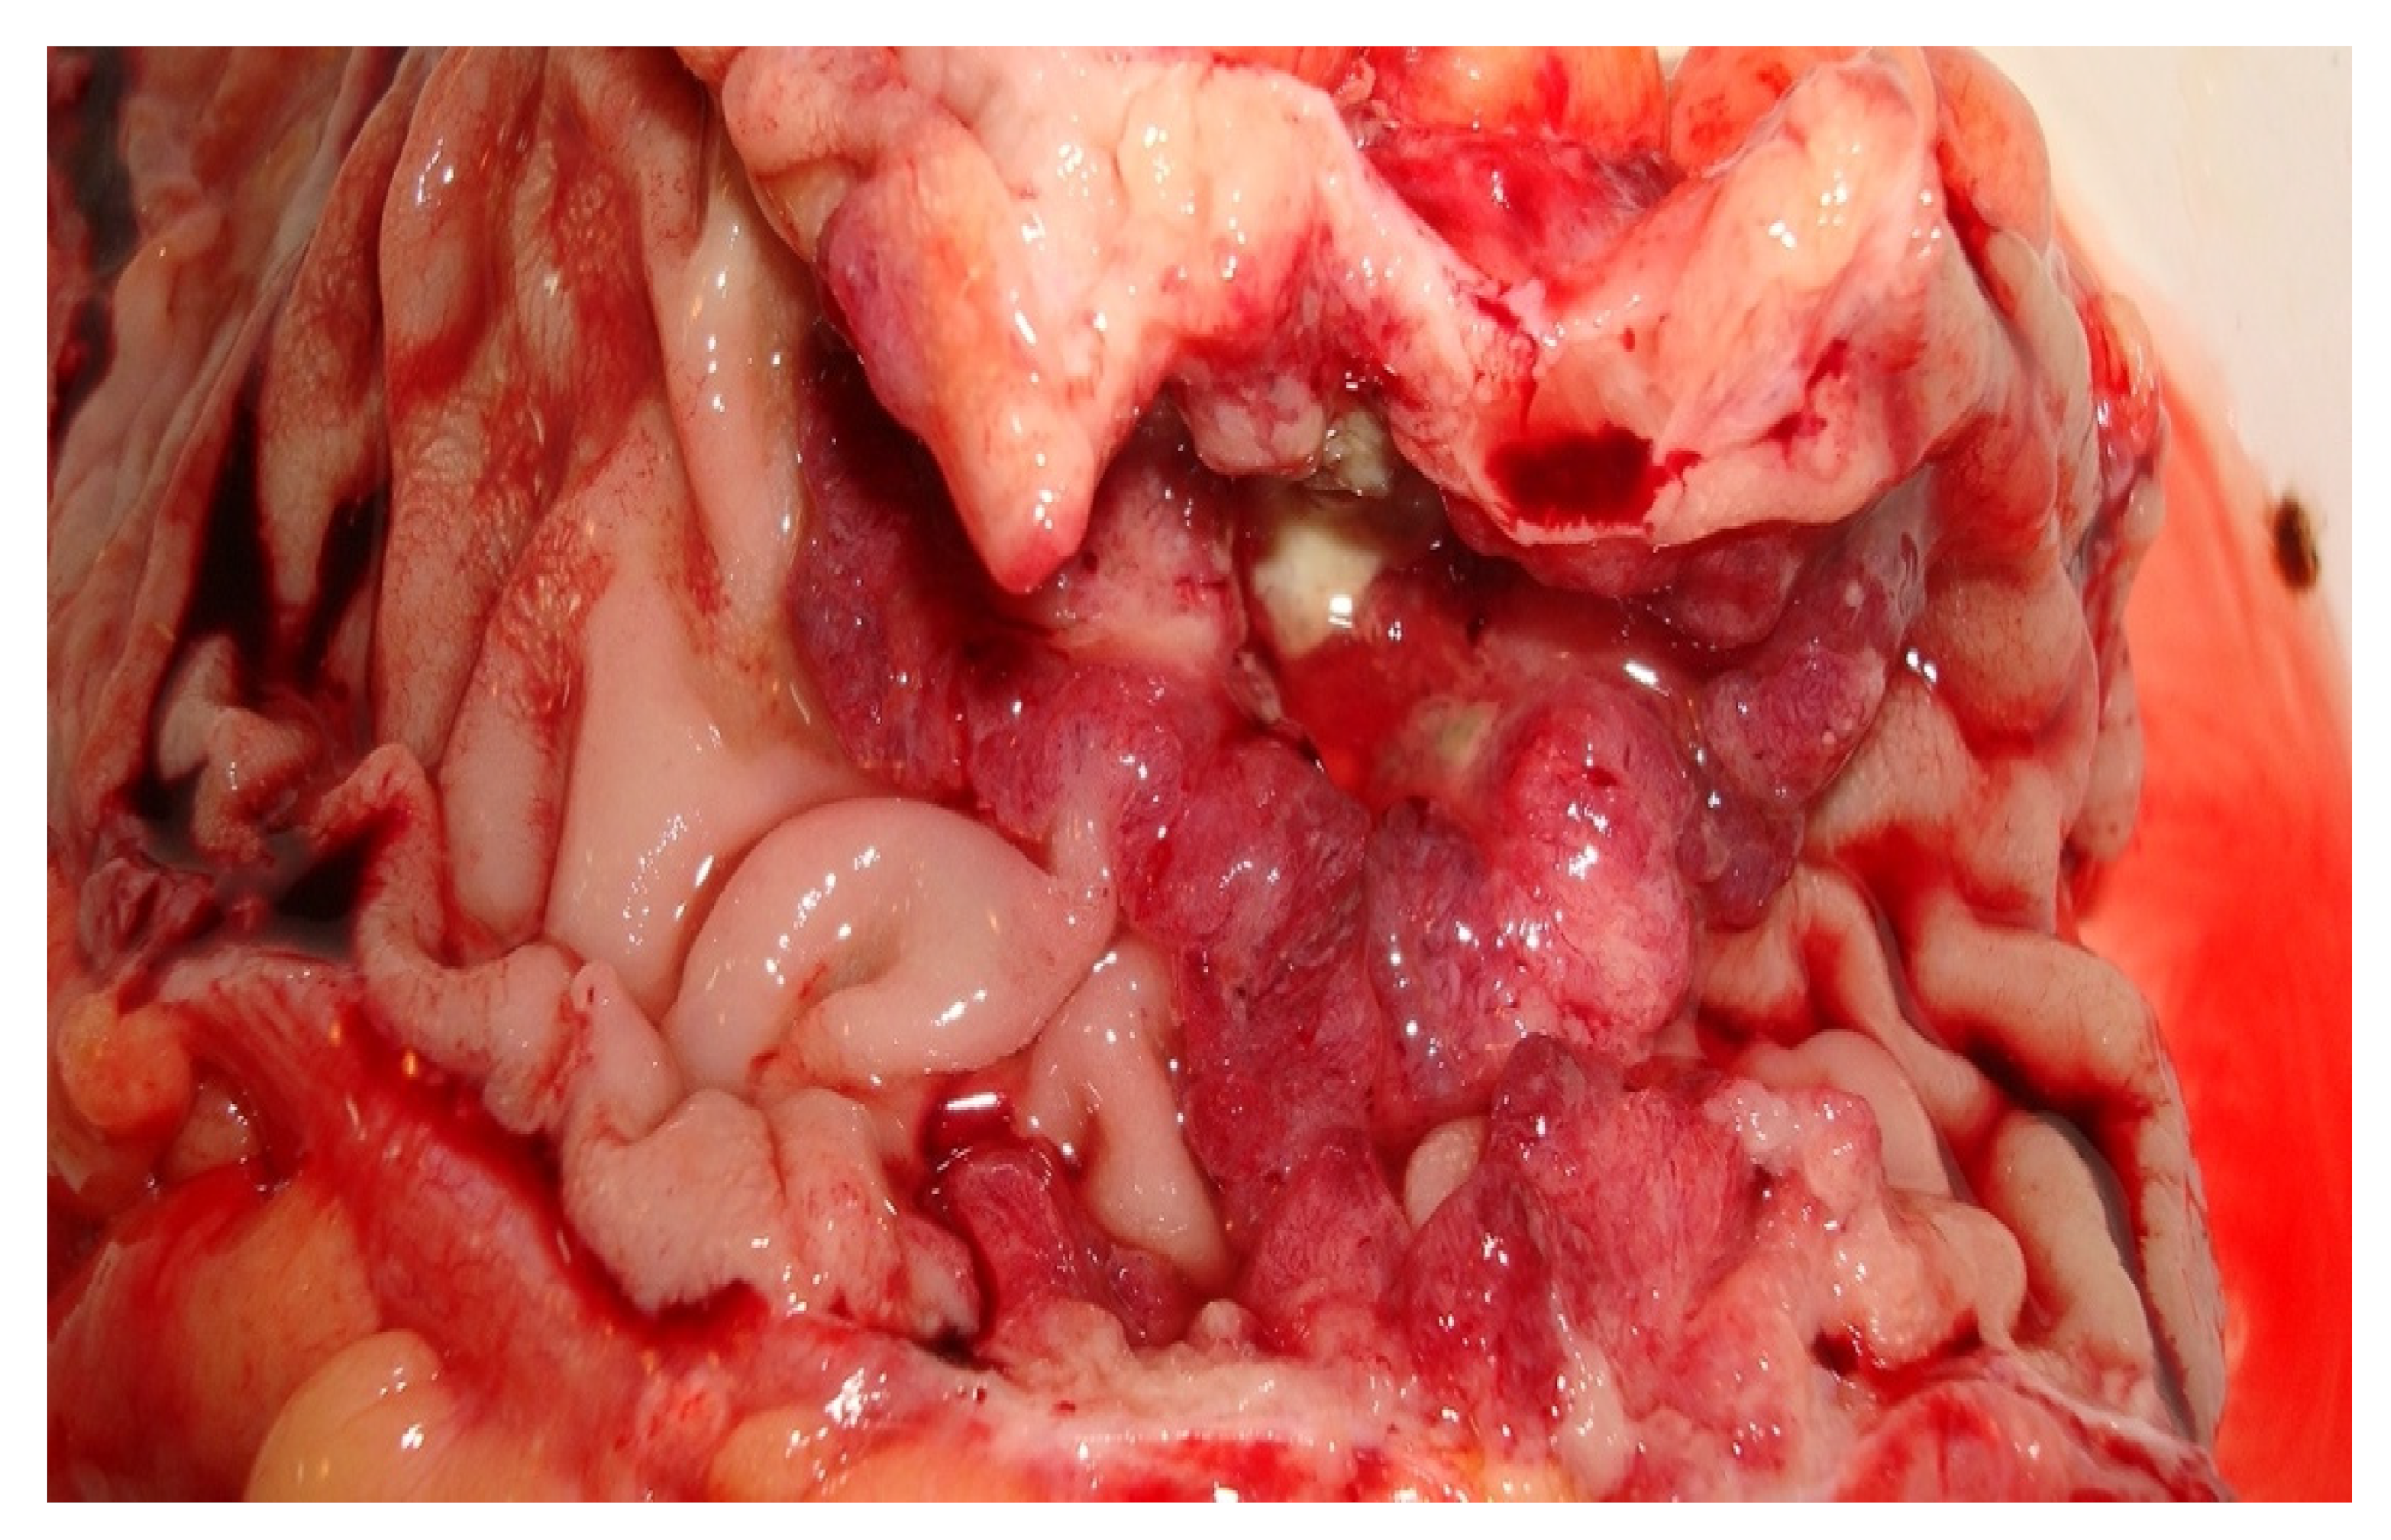

During surgery, after close inspection of the whole abdominal cavity, the team identified a stenosing mass located in the hepatic angle of the ascending colon and subsequent bowel obstruction. We decided that a right hemicolectomy with ileotransversoanastomosis was the best surgical approach for our patient and we performed it.

Figure 1 illustrates the appearance of the portion of the bowel that was surgically resected and was set to the anatomopathological laboratory for histological diagnosis.

Figure 1.

The appearance of the resected portion (2nd Surgery Clinic, patient T.D.).